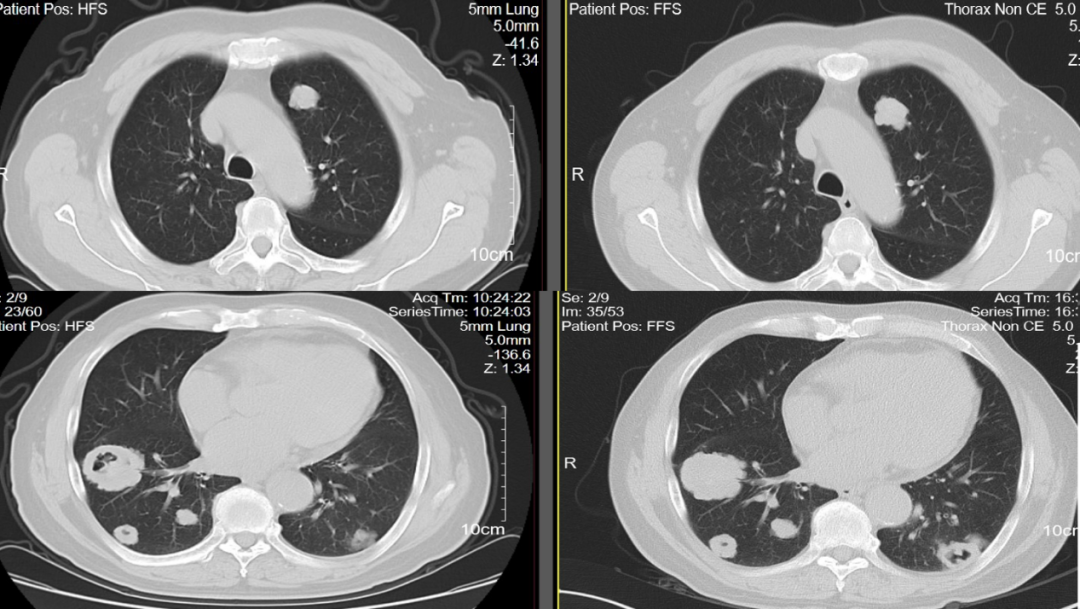

2022年10月13日复查胸部CT检查示,两肺多发转移瘤,部分较前(2022年8月18日)稍增大;2023年1月30日复查胸部CT检查示,两肺多发转移瘤,部分新发空洞形成,范围较前大致相仿(图9)。疗效评估:SD。

图9 胸部CT检查(左:2022年10月13日;中:2022年11月30日;右:2023年1月30日)

其后患者继续接受三线呋喹替尼治疗,于2023年4月11日复查胸部CT检查示,两肺多发转移瘤,部分较前(2023年1月30日)稍增大;心包少量积液,较前相仿(图10)。疗效评估:SD。

图10 胸部CT检查(左:2023年1月30日;右:2023年4月11日)